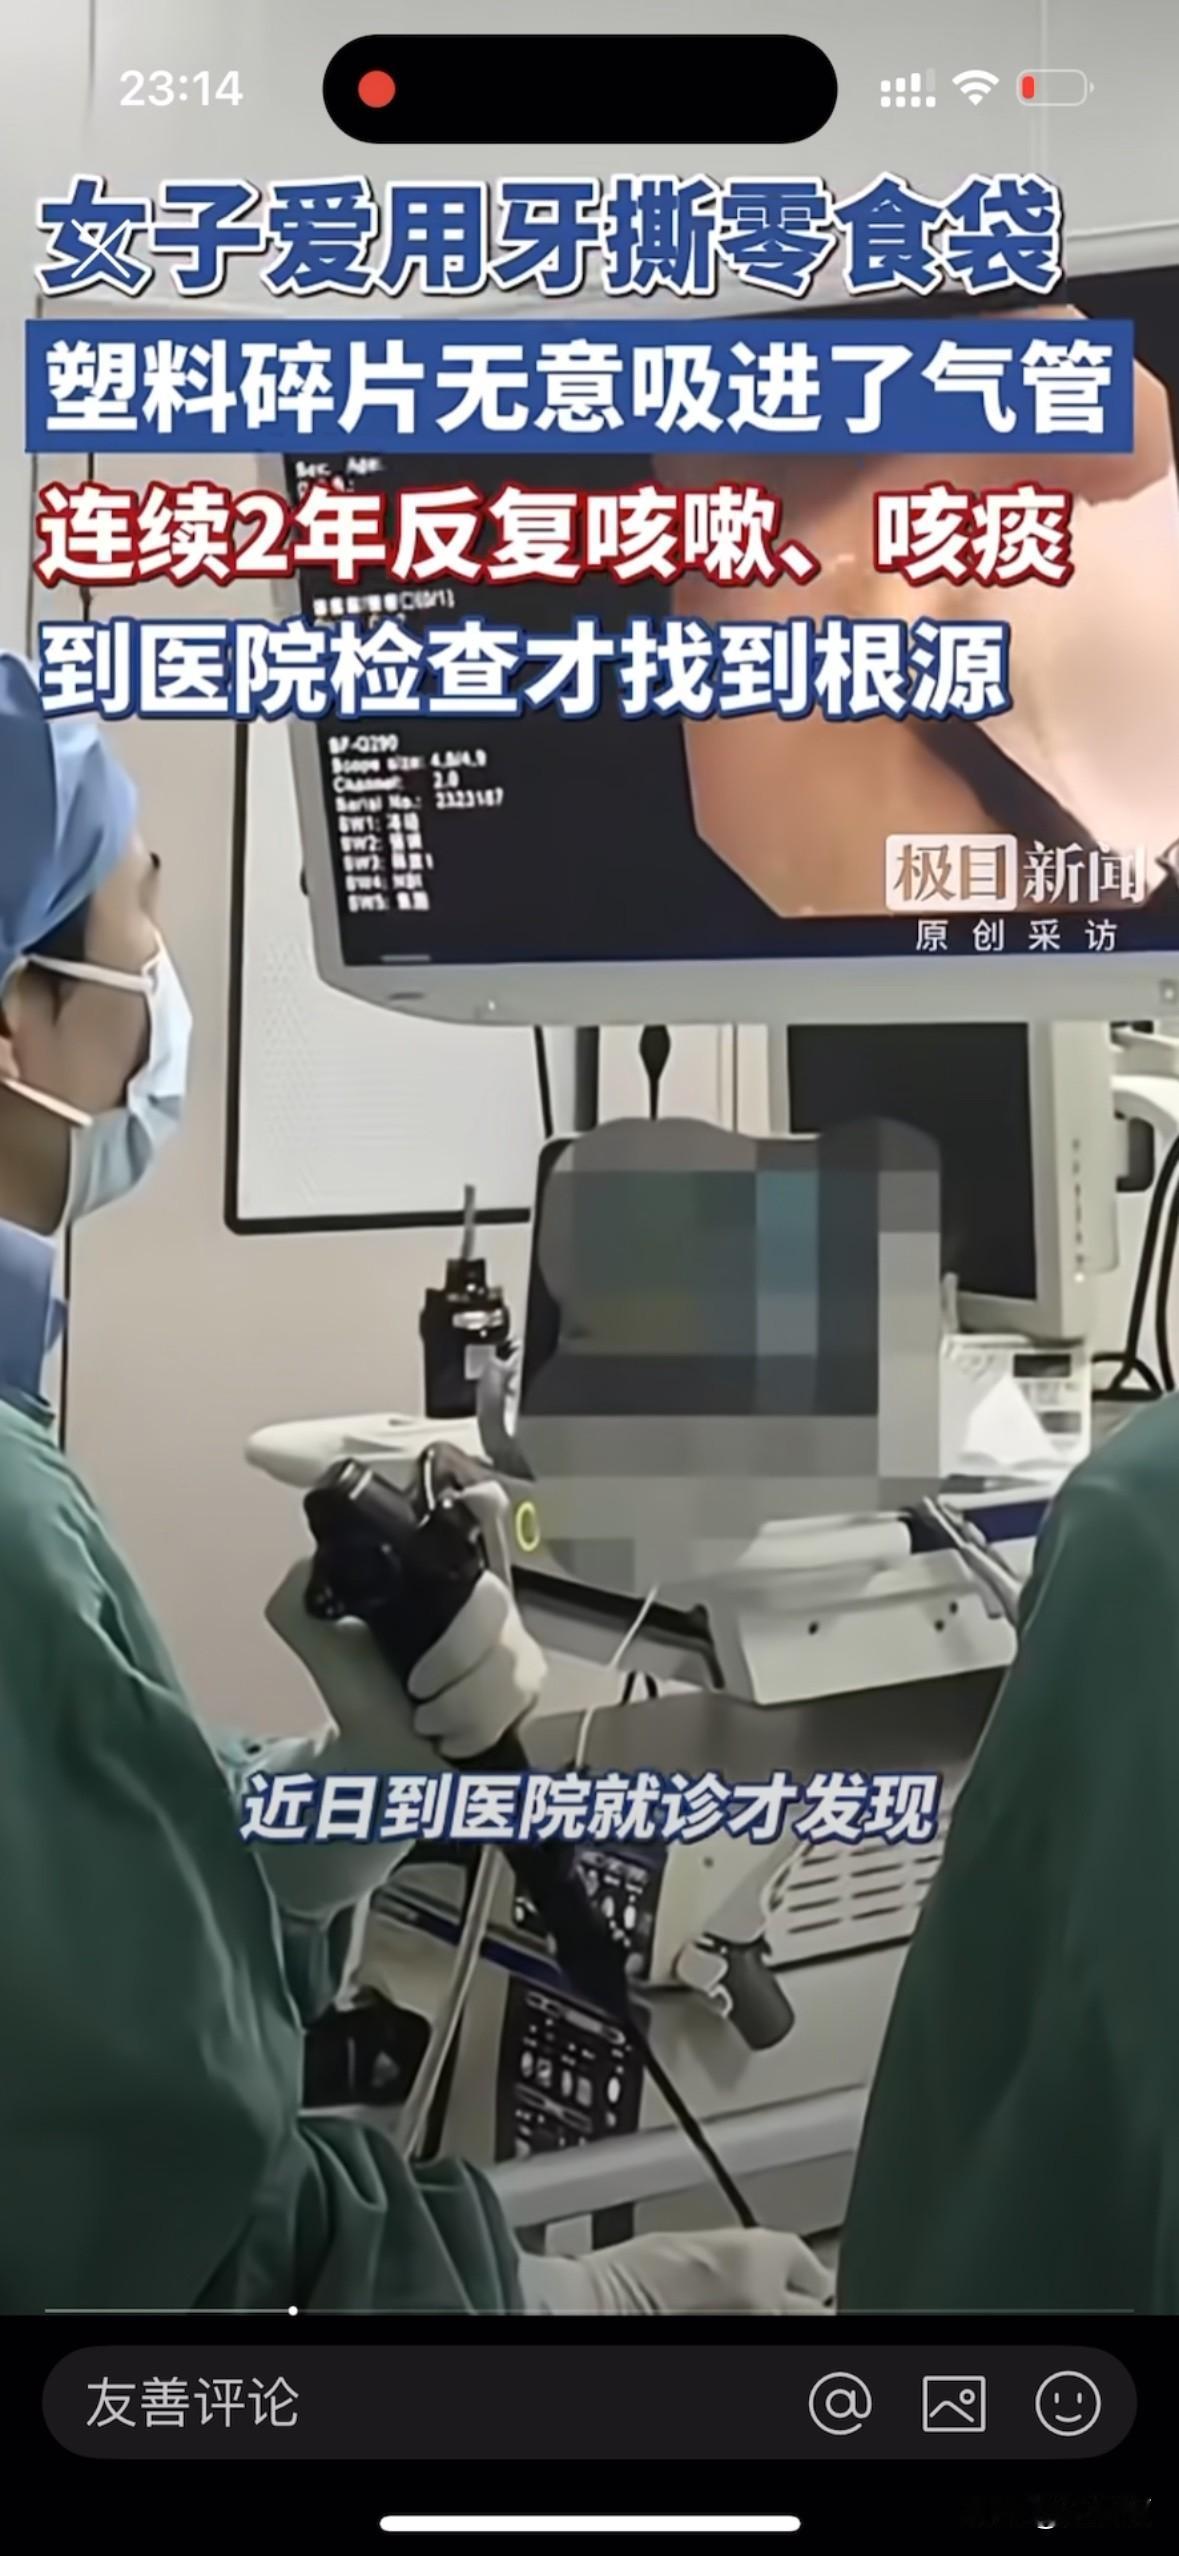

“意想不到有危险⚠️”湖北武汉,一名女子近两年来反复咳嗽、咳痰,不是感冒发烧,嗓子也不痛不痒。近日去医院做检查时发现右下肺支气管深处竟有2块小塑料片。正是这两块塑料片导致她两年反复咳嗽。 现在好多的食品都是即食零食,打开塑料外包装就可以品尝到美味了。打开方式各种各样,有手撕的,有用工具的,更有甚者用牙齿去咬。但方便的同时,也带来了意想不到的危险! 据媒体报道,湖北武汉的李女士从两年前就有点咳嗽,她也没放在心上,以为自己着凉了,引发了炎症,到药店买了点消炎药来吃,吃了几天也就好了。后来多次出现这种情况,李女士便习以为常。 今年冬天,李女士的咳嗽加重了,但除了咳嗽还是没有别的。李女士还是认为自己体寒造成的,便去看了中医,开些中药来调理。 刚开始喝中药时确实有效果,但疗程一结束便复发。 近日,她的咳嗽越来越重,咳出的痰里偶尔还带些血丝。家人劝她赶紧去大医院做检查,劝她有病不能拖,趁着治疗。 李女士到医院一检查,医生发现她右肺下支气管里竟然有两片异物,正是这异物卡在气管里导致她咳嗽。医生通过气管镜手术把异物取出来一看,原来是两块塑料片,塑料片在气管里已经被磨平了棱角! 原来李女士平常在家喜欢吃些袋装的零食,撕不开袋子的时候就用牙齿去咬,有时候碎成小块的塑料袋就随着呼吸进到了气管里。经过治疗,李女士已经康复。 网友:我以前也经常这么干,撕不动就咬开,看了这个视频,以后再也不敢了。 取材网络,侵删